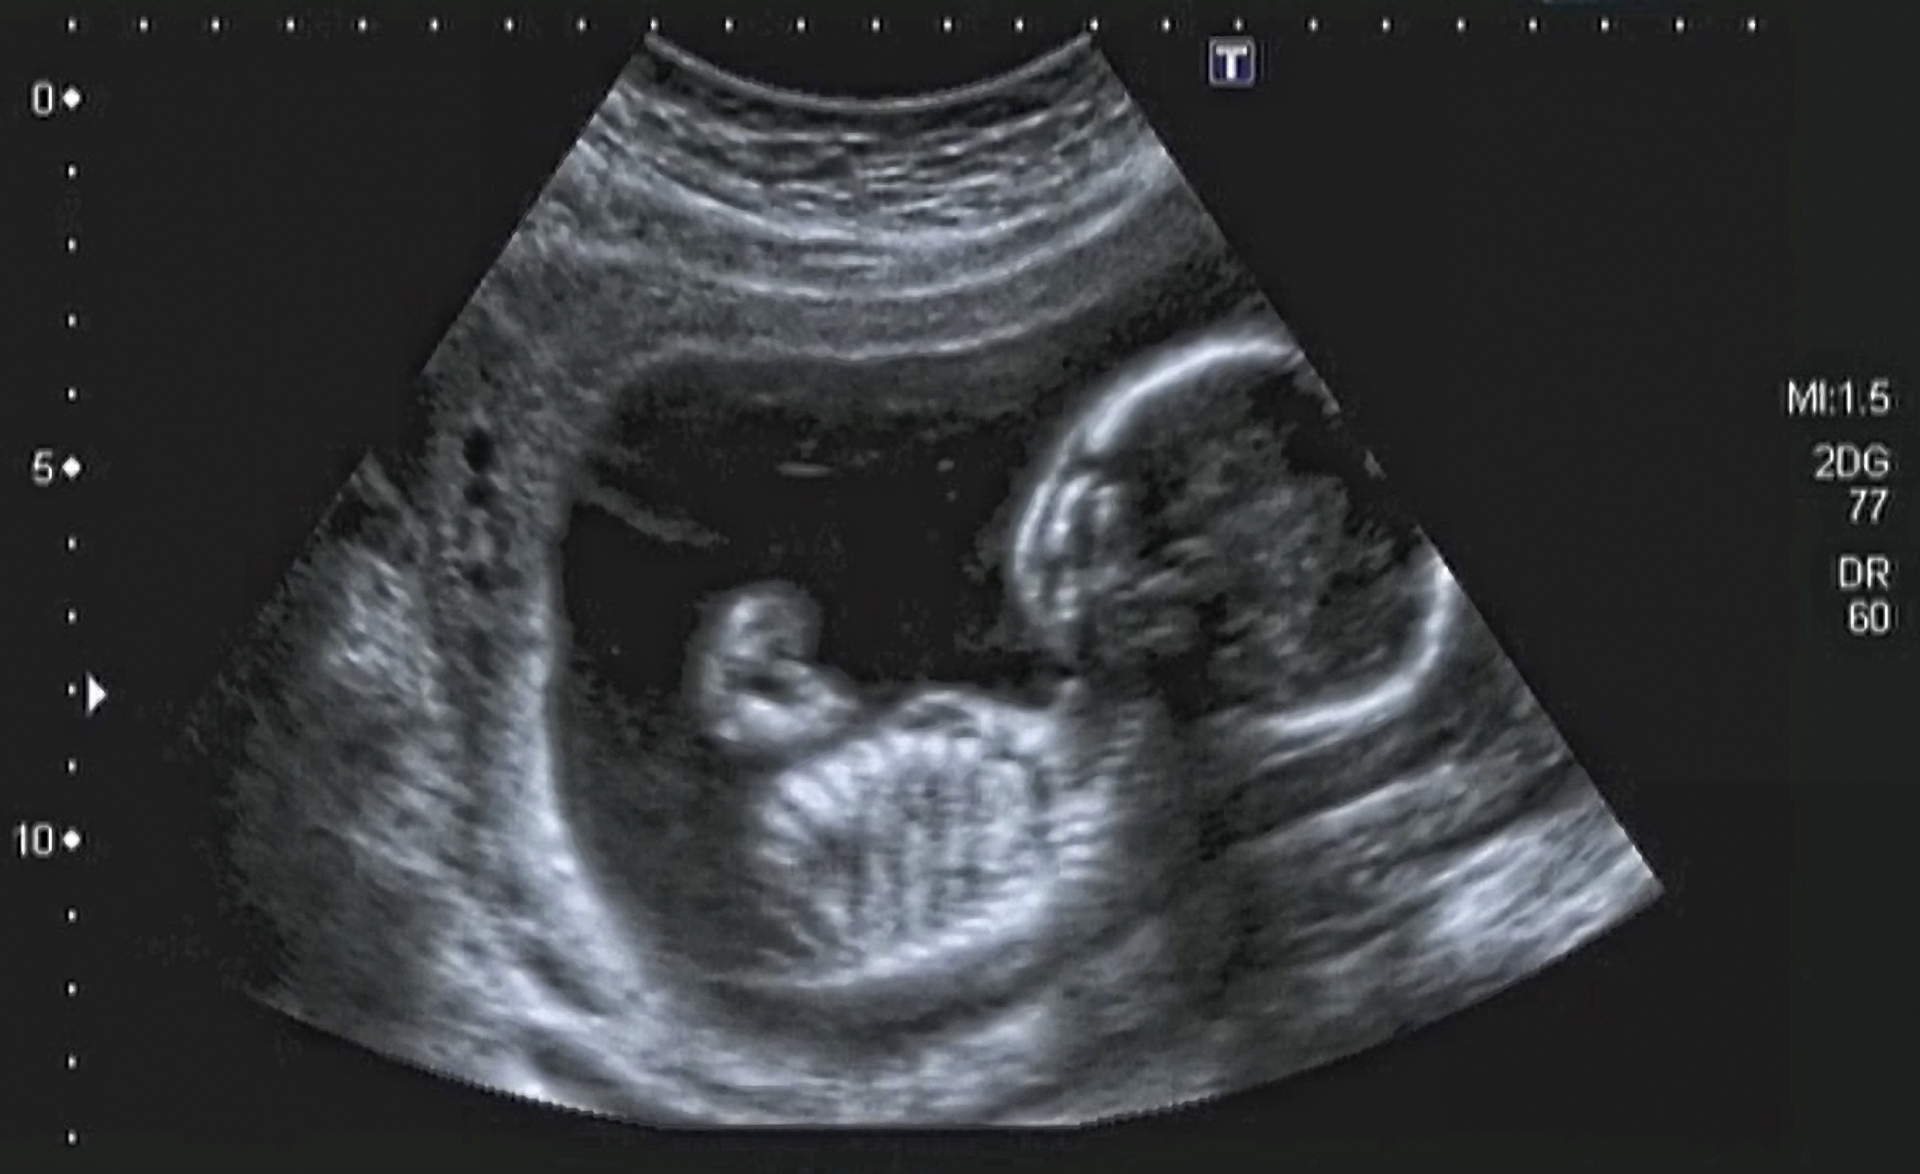

Ultraljudsundersökningar och fosterscreening

Information om ultraljudsundersökningar och fosterscreening under graviditeten

Den andra ultraljudsundersökningen, undersökning av fostrets anatomi

Allmän ultraljudsundersökning och kombinerad screeningundersökning under tidig graviditet

Om ultraljuds- och screeningundersökningar

Avvikande fynd i screeningundersökningar